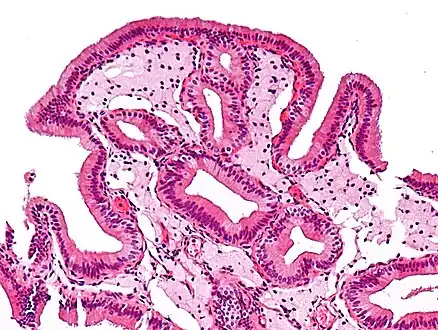

Cholesterolosis of gallbladder

Micrograph of cholesterolosis of the gallbladder, with an annotated foam cell. H&E stain.

In surgical pathology, strawberry gallbladder, more formally cholesterolosis of the gallbladder and gallbladder cholesterolosis, is a change in the gallbladder wall due to excess cholesterol.[1]

The name strawberry gallbladder comes from the typically stippled appearance of the mucosal surface on gross examination, which resembles a strawberry. Cholesterolosis results from abnormal deposits of cholesterol esters in macrophages within the lamina propria (foam cells) and in mucosal epithelium. The gallbladder may be affected in a patchy localized form or in a diffuse form. The diffuse form macroscopically appears as a bright red mucosa with yellow mottling (due to lipid), hence the term strawberry gallbladder. It is not tied to cholelithiasis (gallstones) or cholecystitis (inflammation of the gallbladder).[2]